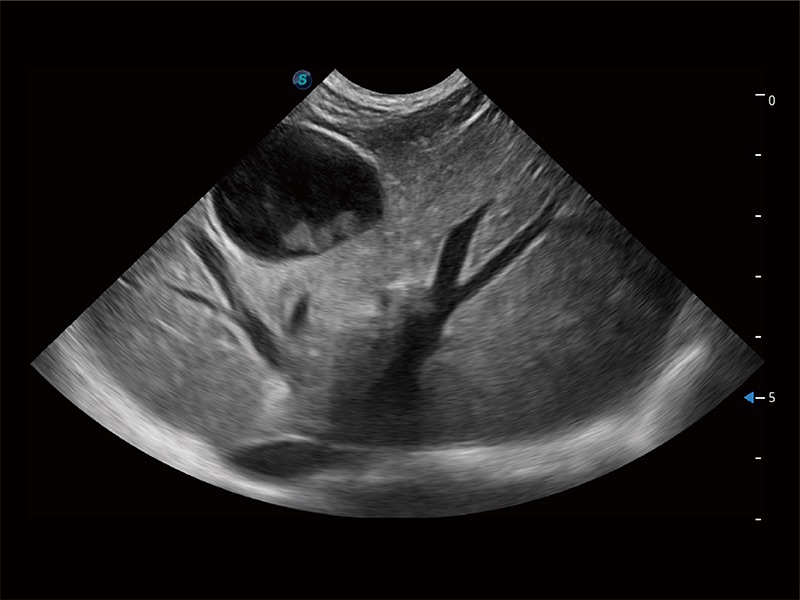

(犬)胎儿四腔心

(犬)胎儿主动脉弓立体血流